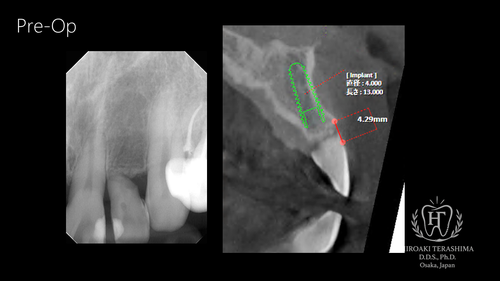

スライド1.PNG

左上前歯は歯根の支持をほぼ失っており、保存は困難な状態でした。

患者さんは長年、接着材で歯を止めながら生活されており、

「いつ外れるかわからない」という強い不安を抱えておられました。

CT(CBCT)および口腔内診査の結果、 抜歯即時埋入インプラントが可能と判断しました。

スライド2.PNG